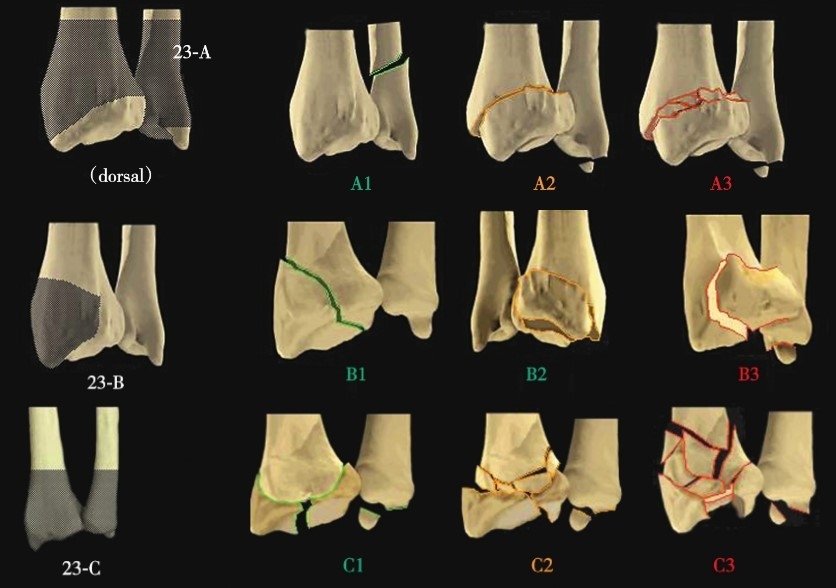

桡骨远端骨折分类方法繁多,常以人名方法命名,例如Colles骨折、Barton骨折(图1)、Smith骨折等。除此之外还包括Mayo关节内骨折分型(图2)、Frykman分型(图3)、AO分型等分类系统。广泛应用的分型是AO分型。桡骨远端解剖部位为23,依累及关节与否及其程度分为A、B、C三个类型(图4)。

图4 AO分型骨折示意图